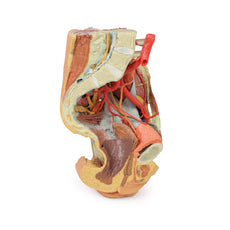

On the right side of the preserved pelvis, the entire femur and thigh musculature has been removed to

demonstrate the obturator membrane, the articular cartilage of the acetabulum and the transverse ligament of the

acetabulum. Posteriorly the entire gluteal region has been dissected to expose the superior gluteal foramen and

the origin of the superior gluteal artery. The sacrotuberous ligament has been removed to demonstrate the

sacrospinous ligament, with some branches of the inferior rectal artery retained within the exposed ischoanal

fossa.

On the left side of the preserved pelvis the sciatic nerve has been maintained within the greater sciatic

foramen, as has the sacrotuberous ligament. The ischioanal fossa mirrors that of the right side, where branches

of the inferior rectal artery have been retained relative to the fibres of the pelvic diaphragm, and the

integration of the external anal sphincter on the projecting external rectal surface.